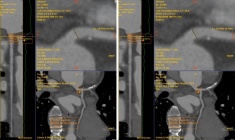

Kết quả chụp động mạch vành cho thấy động mạch liên thất trước (LAD), nhánh quan trọng nhất nuôi tim bị tắc nghẽn tới 99%. Đây là hậu quả của xơ vữa lan tỏa. Trước đó, anh chỉ có những cơn đau thắt ngực nhẹ và nhầm với trào ngược dạ dày.

Can thiệp mạch vành qua da được thực hiện khẩn trương. Hình ảnh chụp DSA xác định hẹp khít 99% đoạn gần LAD thường được gọi là “động mạch của sự sống”. Các bác sỹ đặt stent, tái lập dòng chảy mạch vành, cứu vùng cơ tim thiếu máu cấp và ngăn chặn những cơn loạn nhịp nguy hiểm có thể xảy ra bất cứ lúc nào.